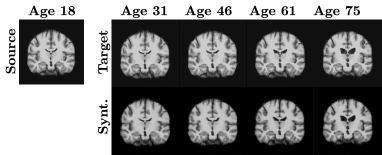

Iconic advancements of generative models in the medical domain have been possible due to several factors, such as state-of-the-art computational hardware and, more importantly, the availability of medical datasets (both open and in-house). Hence, promising solutions for medical image synthesis, restoration, acceleration, and many other tasks have been proposed over the past few years [19]. Recent efforts to generate longitudinal medical images were mainly proposed for the following two tasks: 1) generation of longitudinal brain image [16], which takes a source brain image and generates a new image with respect to chronological age (i.e., normal) progression or disease (i.e., abnormal) progression [11]; and 2) generation of multi-frame cardiac image [4, 12], which typically take a starting frame of a cardiac cycle (i.e., end-diastolic or ED phase) and generates the final frame of the cycle (i.e., end-systolic or ES phase). An illustration showing examples of these tasks is presented in Fig. 1. Generative adversarial networks (GANs) have been a de facto standard for these tasks in the past few years, but recent advances in diffusion models have shown promising results. For example, the latent diffusion model, which uses the latent embedding of an image as input to the diffusion model to improve computational efficiency, has been used to synthesize high-quality 3D brain MRI [17]. Similarly, a diffusion model was combined with a deformation image registration model, namely VoxelMorph [2], to synthesize the end-systolic frame of cardiac MRI [12, 13]. However, most of these works rely on the input from a single image to generate its longitudinal images. Even when longitudinal samples are available, these methods often ignore the sequential dependency in the medical domain.

Refer to caption

(a) Longitudinal Brain MRI

(b) Multi-frame Cardiac MRI

Figure 1: Examples of longitudinal medical images synthesized by our proposed SADM.